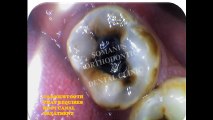

Root Canal treatments- Find the answers for all your concerns here!

This article will alleviate all your apprehension regarding the root canal treatment. This article also advises how to take care your teeth after root canal treatment